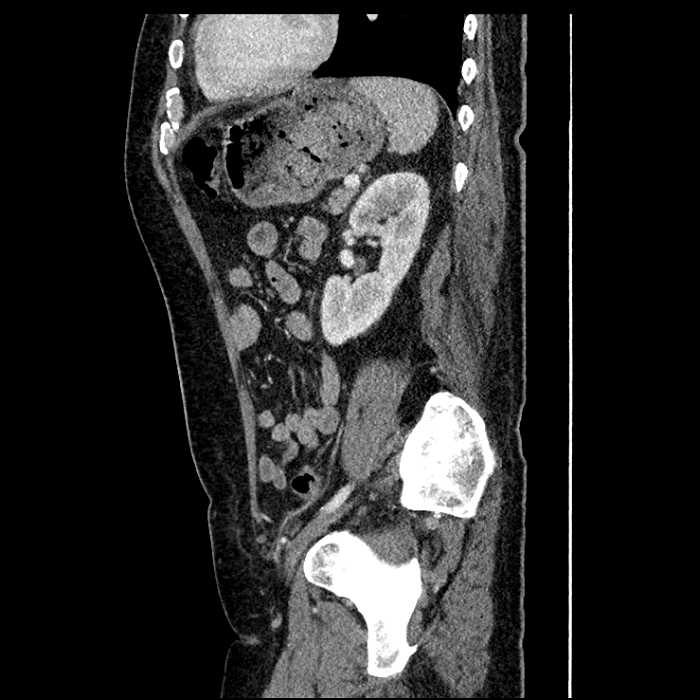

• Large fluid density structure in hepatic segments 7 and 8 measuring 10 x 7 x 7 cm with internal septation and circumferential ill-defined low density compatible with edema

• Peripherally enhancing subcapsular collections along the anterior margin of the left hepatic lobe measuring 3 x 1 cm and 2 x 1 cm

• Clearly marginated fluid density structure in segment 7 and several other scattered tiny hypodensities, which likely represent cysts

• Hepatic abscess

Acute sigmoid diverticulitis complicated by a small contained perforation and a large abscess in the right hepatic lobe. Additional small subcapsular abscesses along the anterior margin of the left hepatic lobe.

• The classic CT imaging appearance is a double target sign with internal low density surrounded by an internal enhancing rim (capsule) and a low density external rim (edema)

Hepatic abscess showing the double target sign with low density internally surrounded by a thin inner enhancing rim (red arrow) and ill-defined outer low density rim (yellow arrow). Blue arrow indicates an internal septation. Red arrows: additional smaller subcapsular abscesses. Red arrow: focal contained perforation associated with diverticulitis.